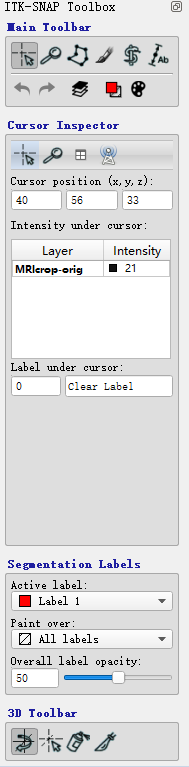

包括四部分:

- ITK-SNAP Toolbox:选择不同的操作模式

- Cursor Inspector:显示目前光标选择的位置以及灰度值

- Segmentation Labels:选择标签

- 3D Toolbar:额外工具

ITK-SNAP Toolbox

1)Crosshairs mode:单击某切片的某像素,可同时查看三个视图上该像素位置的正交视图,按住鼠标坐标不放拖动光标位置,可以连续查看视图变化,鼠标滑轮可以选择当前视图方向上不同的切片

蓝色虚线形成的公共光标始终指向三个切片视图中的相同 voxel,voxel 的灰度级强度和对应的分割标签显示在 Cursor Inspector 面板中

voxel 没有标签时,显示数值 0,对应 “Clear Label”